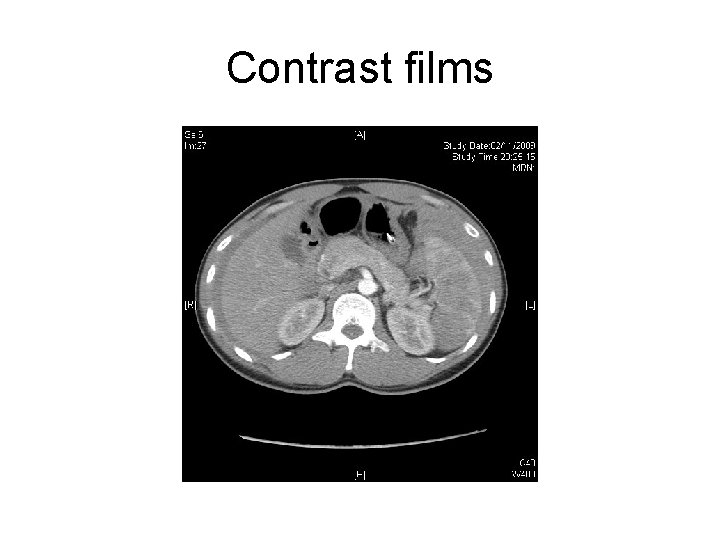

Contrast film

Contrast films

Questions • 1) describe the CT findings • 2) what is the diagnosis? • 3) What is the abnormal CT findings that indicate surgical intervention ? • 4) what is the management?

Answers • Hyperdense peri-splenic hematoma • Scatter intrasplenic hypodense area, suggestive of hematoma and ischemic area • Curvilinear ill-defined hyperdensities are seen within the hypodense region, suggestive of active bleeding • Contrast brush in intrasplenic hypodense area in delay contrast films

• Dx : intrabdominal hematoma due to splenic laceration and presence of active bleeding • Rx : spleenectomy